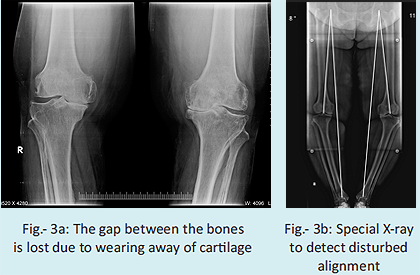

- X-ray should confirm that the knee is permanently damaged and your legs deformed. For this special x- rays are required (Fig-3a,b).

- The damaged joint should be affecting patient's quality of life. This means, he/she should be feeling disabled due to knee problem in activities of day-to- day life. Sometimes, patients themselves find it diffcult to comprehend whether their day-to-day life is disturbed because of the knee. For this, we have devised a scoring system by which the patient tests himself/herself, and thus comes to know of his disability.